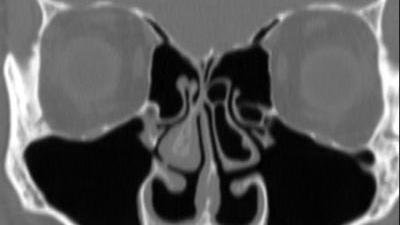

My implant was mistakenly removed during a corrective surgery for sleep apnea, which is one of the side effects of ENS. Since ENS is denied, doctors like my sleep surgeon do not believe that turbinates serve a purpose and that removal can lead to complications. All of the horrible symptoms of ENS have returned since the removal, destroying my sleep, breathing, and quality of life. My breathing is incredibly painful due to dryness and raw, burning pain from excessive tissue removal and nerve damage. I can only sleep a few hours at a time, and I wake up crying with pain, dizzy, nauseated, and exhausted. Many other ENS patients suffer the same life-ruining symptoms and have no access to treatment because of this rule. There is a history of suicide among untreated ENS patients because of the uncontrollable pain and destruction of quality of life - all caused by unnecessary surgery and the unregulated, unsafe practice of turbinectomy.